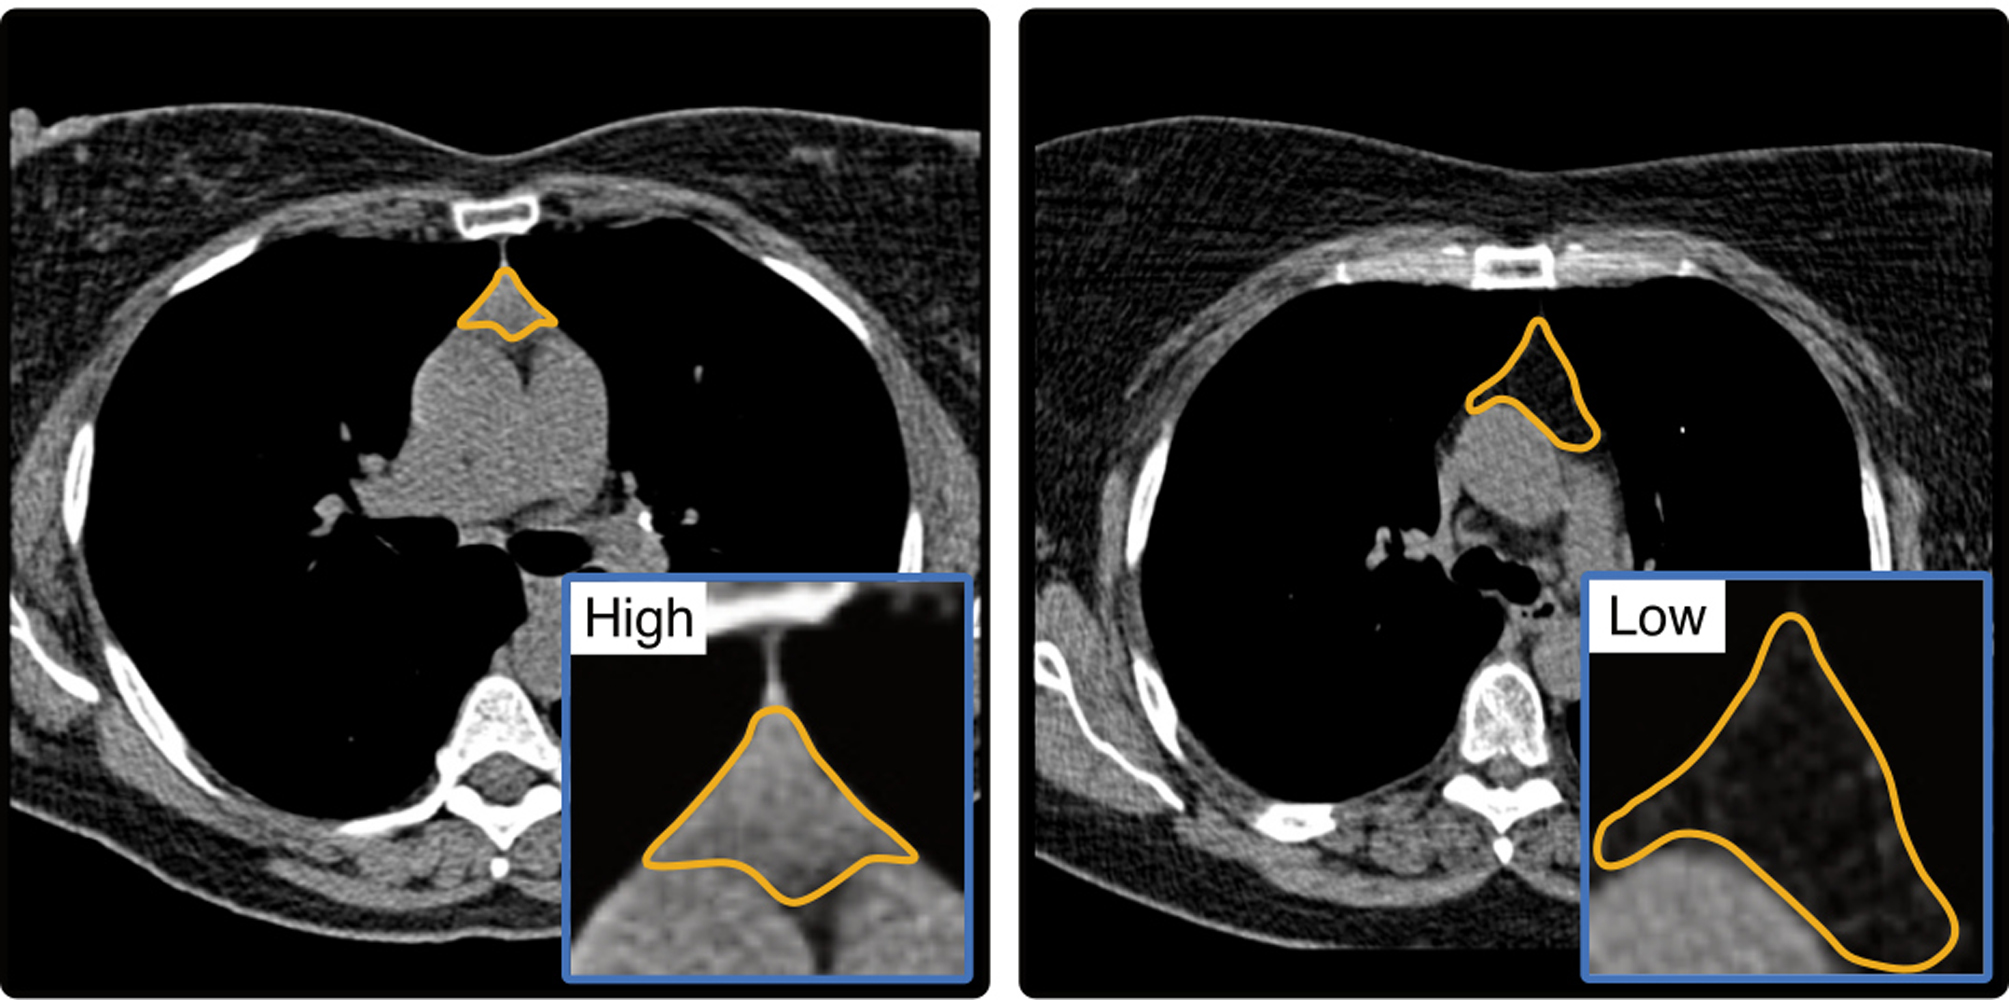

„Die Veröffentlichungen in Nature unterstreichen die außergewöhnliche wissenschaftliche und klinische Relevanz dieser Arbeiten. Sie zeigen eindrucksvoll, welchen Beitrag moderne Bildgebung leisten kann, um bislang unterschätzte biologische Zusammenhänge sichtbar zu machen“, sagt Prof. Dr. Thomas Vogl, Direktor der Klinik für Radiologie und Nuklearmedizin an der Universitätsmedizin Frankfurt. „Wenn es gelingt, die Thymusgesundheit rechtzeitig und zuverlässig zu analysieren, lassen sich individuelle Krankheitsrisiken deutlich früher erkennen und gezielt gegensteuern – lange bevor klinische Symptome auftreten.“ Die Thymusgesundheit, bestimmt anhand routinemäßig erhobener computertomographischer Bilddaten, könnte damit einen neuen Ansatz bieten, Krankheitsrisiken frühzeitig zu erkennen und gezielt präventive Maßnahmen einzuleiten. In der Bildgebung lässt sich die Thymusgesundheit über den Grad der Verfettung beurteilen. Weniger Verfettung spricht dabei tendenziell für eine bessere Immunfunktion.

Zwei internationale Studien unter Federführung der Harvard University (Boston) und weiterer Forschungspartner in Maastricht, Aarhus, London und Frankfurt stützen diese These. Dr. Simon Bernatz, Erstautor der Publikation, Arzt und wissenschaftlicher Mitarbeiter an der Klinik für Radiologie und Nuklearmedizin der Universitätsmedizin Frankfurt, erklärt: „Unsere Analysen zeigen erstmals, dass die Thymusgesundheit ein unabhängiger Vorhersagewert für Überleben und Krankheitsrisiken ist. Besonders bemerkenswert ist, dass wir diese Informationen aus routinemäßigen computertomographischen (CT) Aufnahmen gewinnen konnten.“